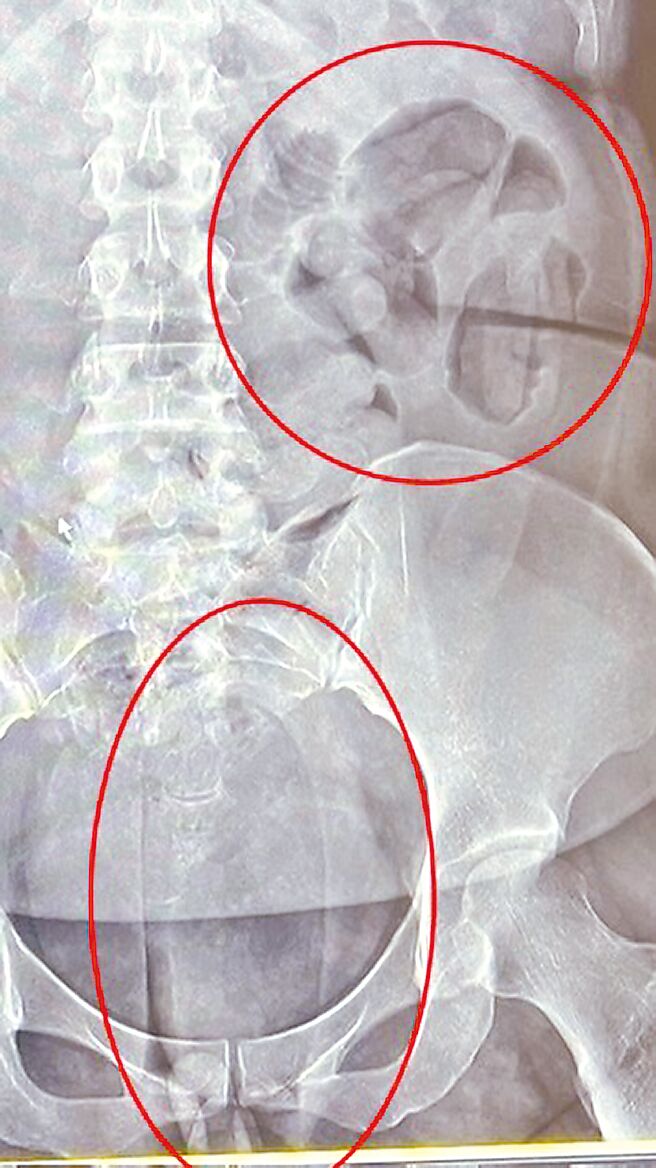

警政署保三总队查获贩毒集团以人体运毒方式,夹带5公斤海洛因与古柯碱等毒品,市值约3500万元。图为夹带毒品X光照。(保三总队提供/徐佑升基隆传真)

保三总队指出,今年5月30日在桃园国际机场查获2名泰籍女犯嫌夹藏海洛因,2人除分别吞下50颗及55颗海洛因胶囊,另在私密处夹藏,总重1755.6公克。保三随即与台北、新北、桃园、高雄等四都及嘉义县等相关警分局,还有移民署台北专勤队成立专案一起侦办,比对案情、地点等关系深入追查。

检警调查,该运毒集团以保险套及热缩膜等层层紧密包装海洛因,压缩成椭圆形球状塞入下体或肛门或口服吞下肚,警方取证时须忍受嫌犯排出毒品的恶臭。